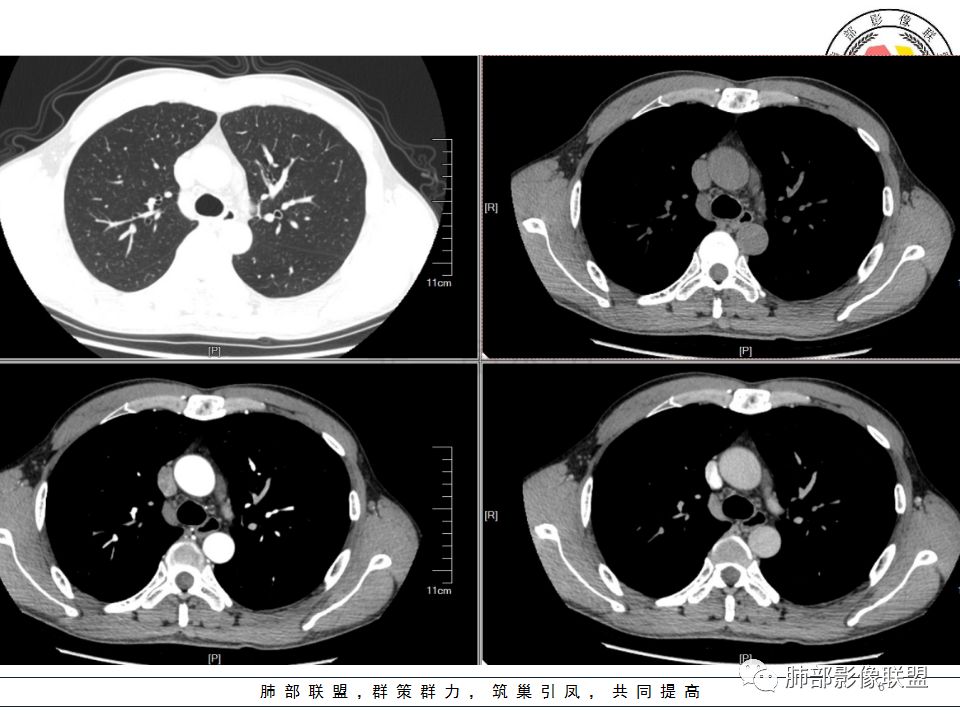

南边:

这是我首先把它定在炎性,附近有一些小卫星灶,我还是倾向结核放在前面,待排恶性肿瘤。刚才有老师考虑隐球,这个就不太支持,因为它的长轴是沿支气管过来的,这明显就不是隐球特点。附近有一些小卫星灶,我还是倾向一个结核的可能性大。

尘缘:沿支气管由外向内的爬行,常规分析还是考虑结核,小细胞癌待排。

炎症结核这种沿支气管爬的,一般是粘液栓,咳嗽咳痰应该有,很少只是胸痛表现

wonderful:答案

支气管树爬行征这个观点是袁怀平老师提出来的。当时提出了一个观点,就是说支气管是通畅的。

现在就是支气管树爬行征的认定问题,就是关于支气管通与不通?如果堵塞,在哪个区域堵塞?

支气管树爬行征就是肉芽肿性病变,不过它是沿着支气管周围间质往里面走的。我们以前认定支气管要通畅的,但是我们读了隐球菌发现,包括肺炎性肺癌,你就发现外围的病变往内带进展,可以支气管堵塞,例如隐球菌有个特点非常明显的,一个大片状影,支气管在中近端堵塞。我们反推过来,结核也可以这样变化;支气管爬行征原来是要求支气管通畅,改良为支气管可以通畅,也可以在中间堵塞。

该如何判断支气管树爬行征,还需要大宗数据进行观察总结。

支气管树爬行征:肺内结核性肉芽肿的特征性CT征象之一